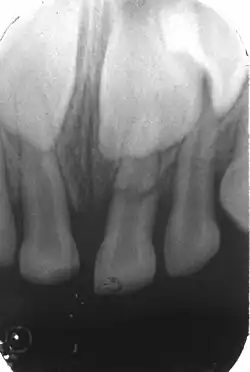

Luxation latérale

C'est un déplacement non axial de la dent souvent accompagné d'une fracture alvéolaire. Dans ce cas la dent n'est pas dans l'axe des autres, il y a un saignement autour de la dent, une douleur spontanée ou provoquée par une simple pression. Si on a une luxation latérale seule, parfois on a une absence de sensibilité et de mobilité, donc on a une luxation latérale pure sans fracture alvéolaire, sans écrasement d'os. Attention bien faire le diagnostic différentiel avec une mobilité due à une fracture radiculaire.